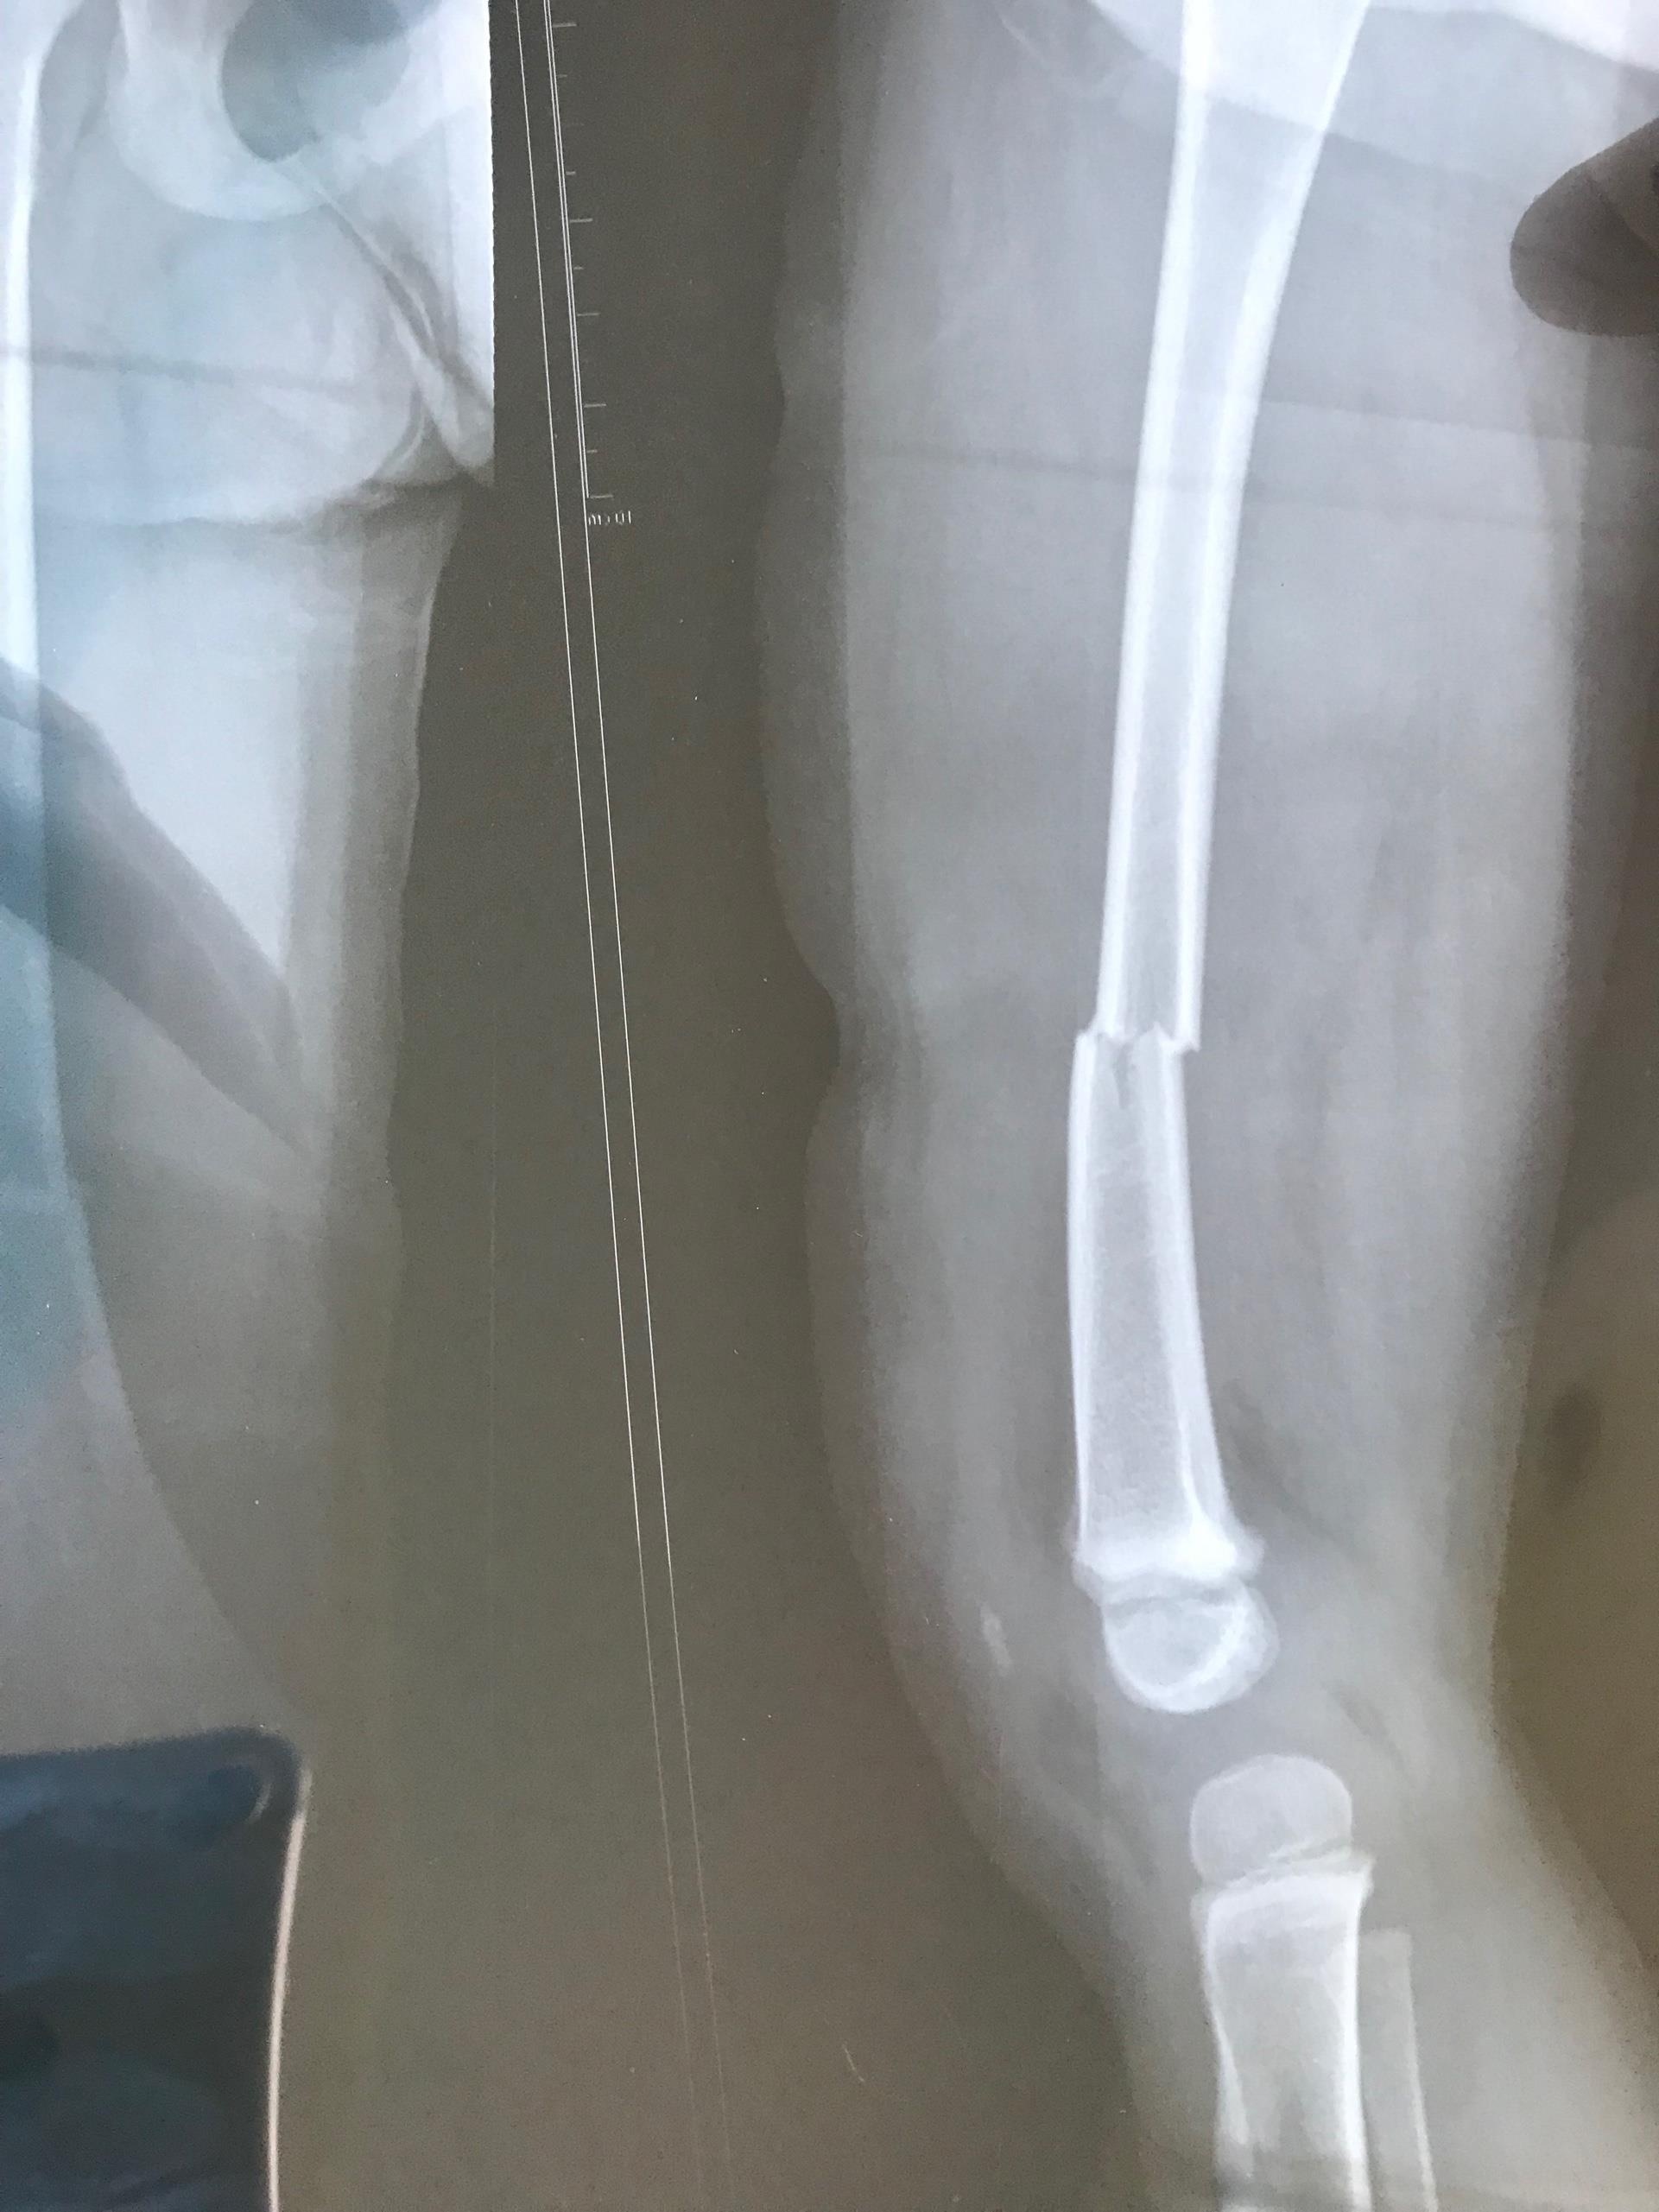

| Ảnh chụp X-quang cháu bé gãy xương đùi bên trái. Ảnh: GĐCC. |

Các bác sĩ cho biết M.A. bị gãy xương đùi bên trái do va đập mạnh, cần nẹp sơ cứu để phẫu thuật.